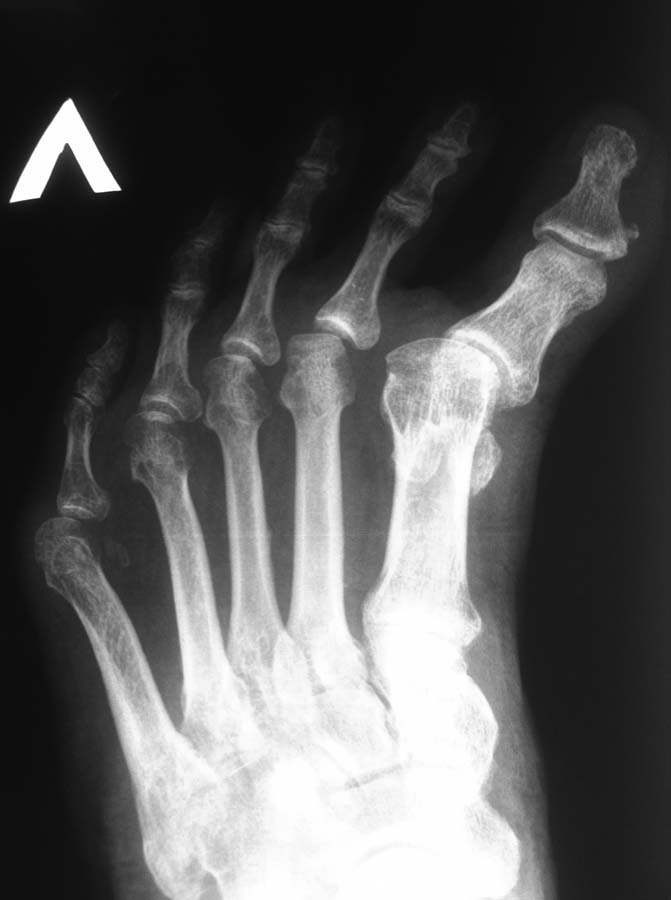

Могу сообщить из личного опыта. Больной 65 лет, страдает артрогрипозом. Стопы не оперированы. Рентген аналогичный. Деформация стопы многокомпонентная многоплоскостная: эквино-поло-варусная, приведение переднего отдела, варусная когтеобразная деформация 1 - 5 пальцев.